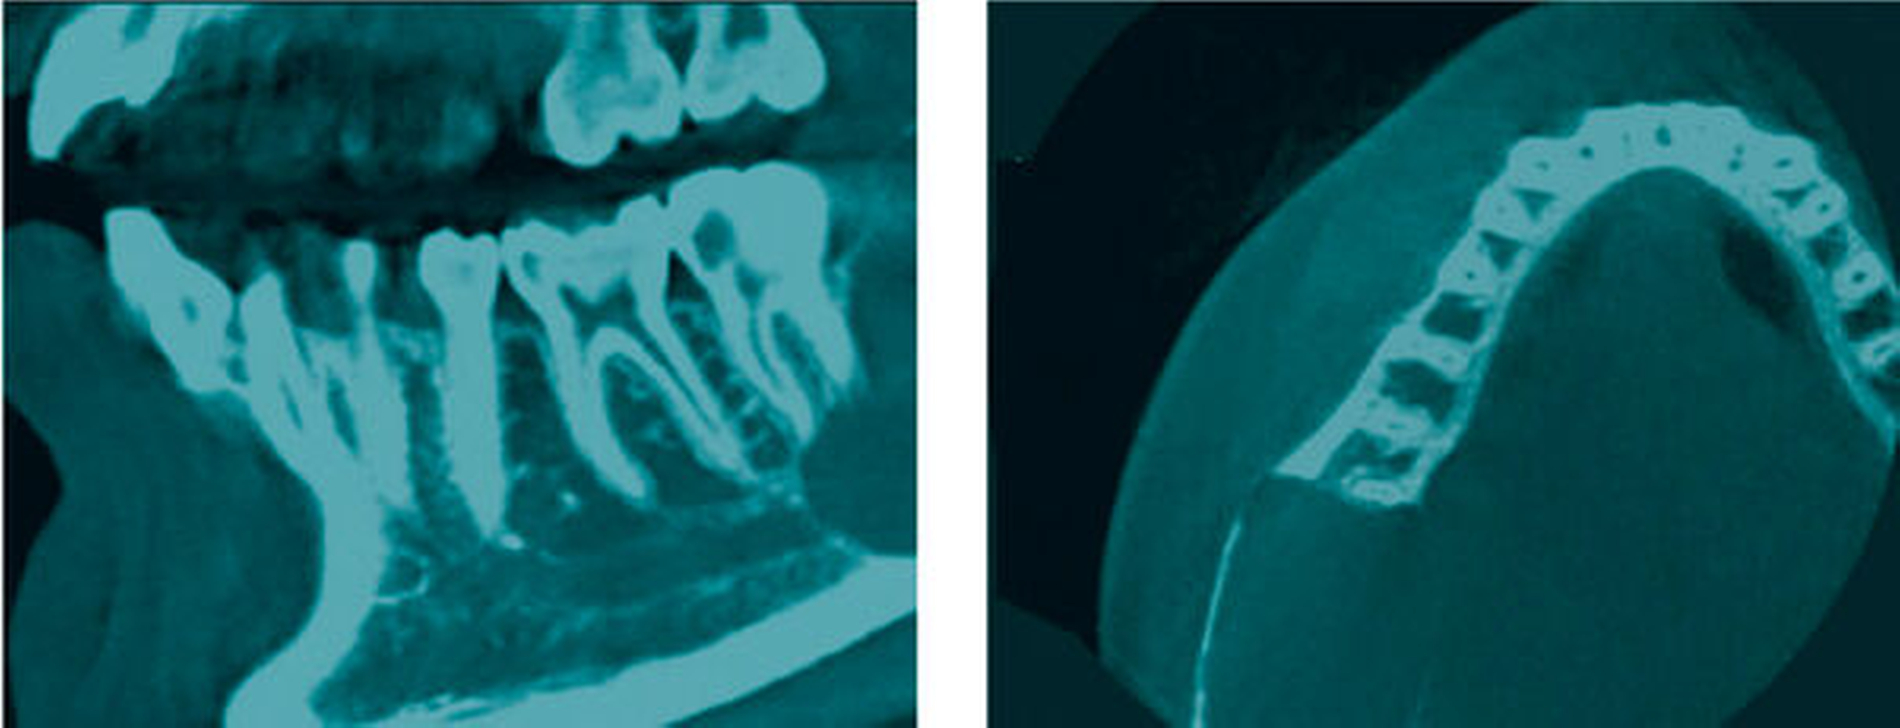

Zur Beurteilung der Befundausdehnung und Planung der Therapie wird eine Digitale Volumentomografie (DVT) des Mittelgesichts inklusive Unterkiefer angefertigt (Abbildung). Hier zeigen sich die vestibuläre und linguale Compacta massiv atroph und crestal sowie lingual bereits perforiert. Die Lage des Nervus alveolaris inferior projiziert sich kaudal des Befunds und erscheint in seinem Verlauf nicht verdrängt.

Wie im vorliegenden Fall ist die Mehrzahl – etwa 80 Prozent – der Ameloblastome im Bereich des Kieferwinkels lokalisiert [Reichart et al., 1995]. Hier korreliert das radiologische Erscheinungsbild einer scharf begrenzten unilokulären, zystenähnlichen hypodensen Struktur (Abbildung 2b) mit der histopathologischen Diagnose des unizystischen Ameloblastoms.